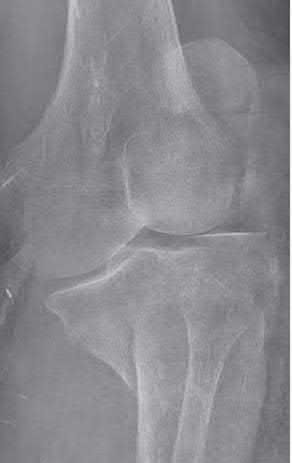

Question 1:

A 12-year-old obese boy presents with vague left thigh and knee pain. He is diagnosed with a Slipped Capital Femoral Epiphysis (SCFE) as seen in similar clinical scenarios. During percutaneous in-situ fixation, unrecognized penetration of the guide wire into the hip joint occurs. What is the most likely specific complication resulting from this technical error?

Chondrolysis is a severe complication of SCFE characterized by rapid destruction of the articular cartilage. While it can occur idiopathically, its most established iatrogenic cause is unrecognized intra-articular hardware penetration. The 'approach-withdraw' fluoroscopic technique is required during pinning to assure pins are entirely intraosseous. Avascular necrosis (AVN) is usually due to damage to the epiphyseal blood supply (retinacular vessels) secondary to the initial displacement, forceful closed reduction, or posterosuperior pin placement.